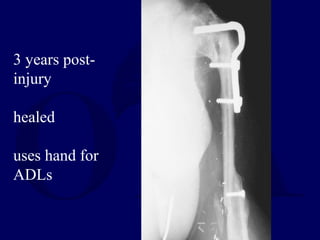

3 years post-

injury

healed

uses hand for

ADLs